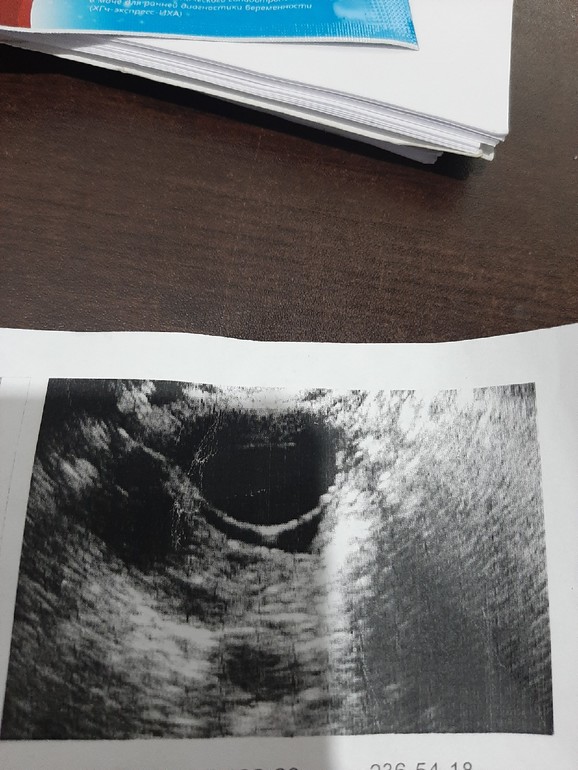

Правый яичник увеличен энэхогенное образование 32*27*31мм

Заключение: фаликулярная киста правого яичника

Собственно фото кисты и самих тестов